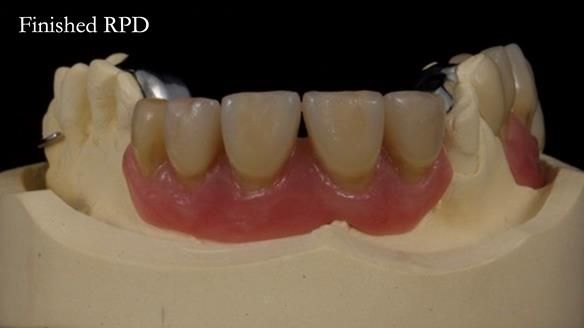

Keith’s combat denture case study

Keith’s case was one of the most challenging and rewarding cases I’ve treated this year. This 64 year old man presented with ill-fitting acrylic partial dentures that lacked stability, retention, and aesthetics. They constantly broke. He had lost the upper front teeth in a road traffic accident in his early 20s. The unopposed teeth had erupted, taking up space. After careful planning, we made a durable, metal-based upper partial denture/splint to address his dental concerns. He loved the outcome.

1. Denture design: A custom cobalt-chromium framework was Scandinavian-designed to maximise stability, protect the remaining teeth, and allow for future additions if needed.

Keith’s denture incorporated a Duracetal shell clasp on upper right first premolar (Myerson), which are designed to be virtually visible, providing a more aesthetic solution while enhancing patient comfort. The Scandinavian-inspired approach, based in modern removable prosthodontic techniques, ensured the denture was not only durable but also visually pleasing. Additionally, the design was carefully planned to allow for future modifications, ensuring that if Keith loses additional teeth, the denture can be adapted rather than replaced entirely.